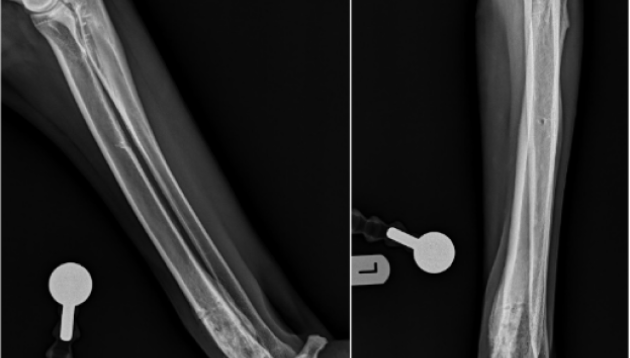

Se realizaron radiografías del antebrazo afectado, en las que se observaron reacciones periódicas en la región diafisaria distal del radio con un aumento de la densidad de los tejidos blandos adyacentes a ésta. Ante la sospecha de una lesión agresiva ósea (posible neoplasia – tumor) tomamos una biopsia ósea del tejido afectado. Los hallazgos histopatológicos de ésta, fueron compatibles con un osteosarcoma osteoblástico de grado II.

En el caso de Leo, una vez confirmado el diagnóstico de osteosarcoma, realizamos un estudio tomográfico tanto del miembro afectado como del tórax y el abdomen. En las últimas dos regiones se descartó la presencia de metástasis. Tras estudiar las diferentes alternativas terapéuticas, y exponer todos los detalles, su familia optó por la realización de una técnica de salvación de miembro (Limb Sparing), con la finalidad de mejorar la funcionalidad de Leo.